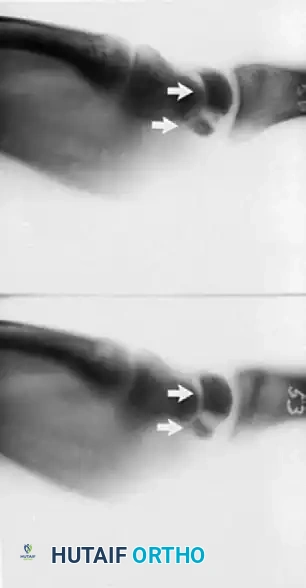

Fractures of the lunate are notoriously difficult to detect on standard posteroanterior (PA) and lateral plain radiographs due to the superimposition of the radial styloid, scaphoid, and triquetrum.

- Advanced Imaging: Thin-slice computed tomography (CT) or complex motion tomography is frequently required to definitively identify and characterize the fracture pattern.

- Fracture Patterns: Lunate fractures may present as nondisplaced, displaced with large fragments, avulsed (especially at the dorsal pole where critical radiocarpal ligaments attach), or highly comminuted.

Armistead et al., utilizing CT imaging, demonstrated that occult fractures of the lunate are present in a significant subset of Kienböck patients.

A common fracture pattern is the anterior pole type, which isolates the anterior pole from the remaining bone. The compressive force exerted by the capitate distracts the fracture, diminishing the likelihood of healing. As the dorsal portion of the lunate collapses, the anterior pole may be extruded volarly. Furthermore, the ratio of carpal height to the length of the third metacarpal is reduced (normal is 0.54 ± 0.03), indicating overall carpal collapse.